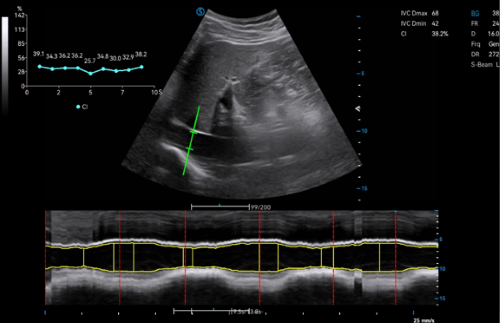

Apogee 1000 Plus

Apogee 1000 Plus is a highly cost-effective entry-level ultrasound imaging system. With its lightweight, splash-proof, and dust-proof design, it adapts well to bedside examinations, emergency rescue, and other challenging environmental settings. Powered by the advanced Realview+ platform, it provides satisfactory image quality, comprehensive applications, and streamlined workflow, offering enhanced operational experience for primary healthcare.

Function

VS Flow is highly sensitive to low velocity blood flow signal and especially suitable for superficial blood flow examination

Auto OB automatically measures the fetal biometric results (e.g. HC, BPD, FL) in standard sections, while AUTO NT measures the thickness of nuchal translucency

Auto Flow automatically adjusts the sampling frame to better capture the blood flow signal, while Auto Fit intelligently optimizes the image display through one click